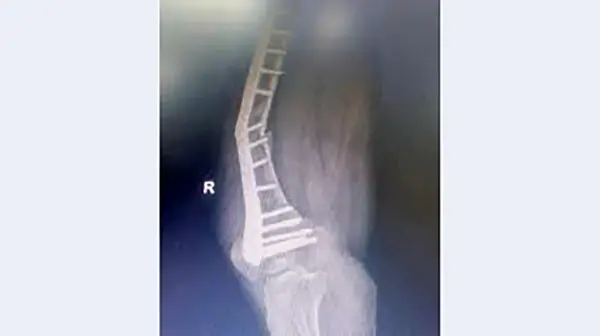

حوادث رکنا : دوم شهریور گزارشی با عنوان «جنجال پلاتین های مشکوک» منتشر شد که بیانگر کج شدن پلاتین های بیمارستانی در بدن بیماران بود.

به گزارش رکنا، در این گزارش چند بیمار به طور اتفاقی با یکدیگر در بیمارستان دولتی نیشابور برخورد می کنند که با عوارض مشابهی بعد از انجام عمل جراحی و پلاتین گذاری در پا روبه رو شده و دوباره به بیمارستان مراجعه کرده بودند.

پلاتین های بیمارستانی بنا به اظهارات بیماران کهن سال در پای آن ها کج شده بود و با عوارض وحشتناکی دست و پنجه نرم می کردند. طبق اظهارات همراهان بیمارانی که خبرنگار روزنامه خراسان با آن ها مصاحبه کرده است خرید پلاتین ها از شرکتی بوده که مدیران درمان نیشابور قصد ندارند نام آن را افشا کنند و این ماجرا از پشت پرده هایی حکایت دارد که باید مسئولان نظارتی و مدعی العموم به پیگیری آن بپردازند.